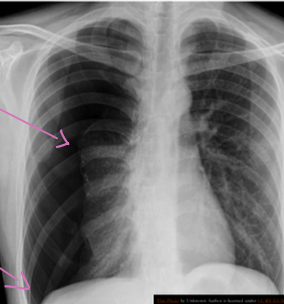

Case 5

Patient present with acute chest pain..

Diagnosis?

- Pneumothorax

What abnormalities do you see?

- lucency of hemithorax

- absent broncho-vascular markings Z

- shifted trachea to the right

Predisposing causes?

- Trauma

- Ruptured alveoli

- Cystic fibrosis

important and prompt steps of management

- (Needle decompression) needle in the second intercostal space midclavicular line to decompress.

- Tube in the 5th intercostal space, anterior axillary line, pushed to the back and upward.